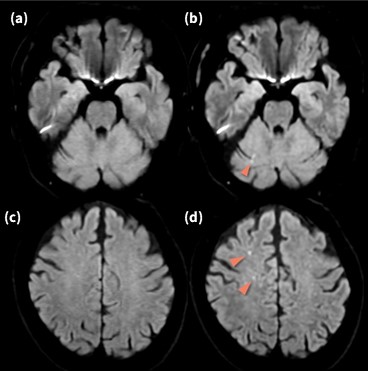

SIGNA™ Voyagerは静磁場均一性に優れていることから、SI方向における広範囲撮像を得意とする。Fig.1に腰椎圧迫骨折に対して胸腰椎をFOV50cm の1ステーション にて撮像した画像を示す。位相方向をSIにしているにも関わらず、アネファクトや折り返し等のアーチファクトが抑制され、また脂肪抑制画像ではSI方向両端においても均一に脂肪が抑制されていることがわかる。これは、良好な静磁場均一性に加え、GEHC社独自の技術であるTDI(Total Digital Imaging)や後述するAIR™ Recon等の相乗効果と考える。広範囲撮像の安定性が図られたことで、当院では胸腰椎撮像の際、確実な病変の拾い上げを行うためlarge FOV で1ステーションの撮像をルーチン化し、またステーション数減少による撮像時間の短縮を図っている。昨今、Deep Learning等の最新技術がフォーカスされるが、GEHC社オリジナル技術は新技術の基盤となっており、安定した画質を支えている。

VoyagerMR30_ube02.jpg

Fig.1 腰椎圧迫骨折に対しFOV 50cm 1station にて撮像した胸腰椎画像

(a) T2 FSE (b)T2_STIR FSE (c)T1 FSE